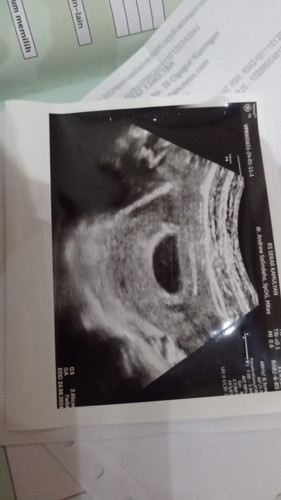

Hallo bun barangkali ada yang sama kasusnya kaya aku, jd kmren pas 7w4d aku d vonis BO dan harus kuret, tapi aku minta d evaluasi lagi dan 2 hri sblm USG aku ada flek tp cuman segaris aja dan ga banyak bun.. Jd Apakah ada harapan kalo BO dan akhirnya berkembang lagi.. Brbagi pengalamannya bun.. Mksh # ##seriusnanya #bantusharing